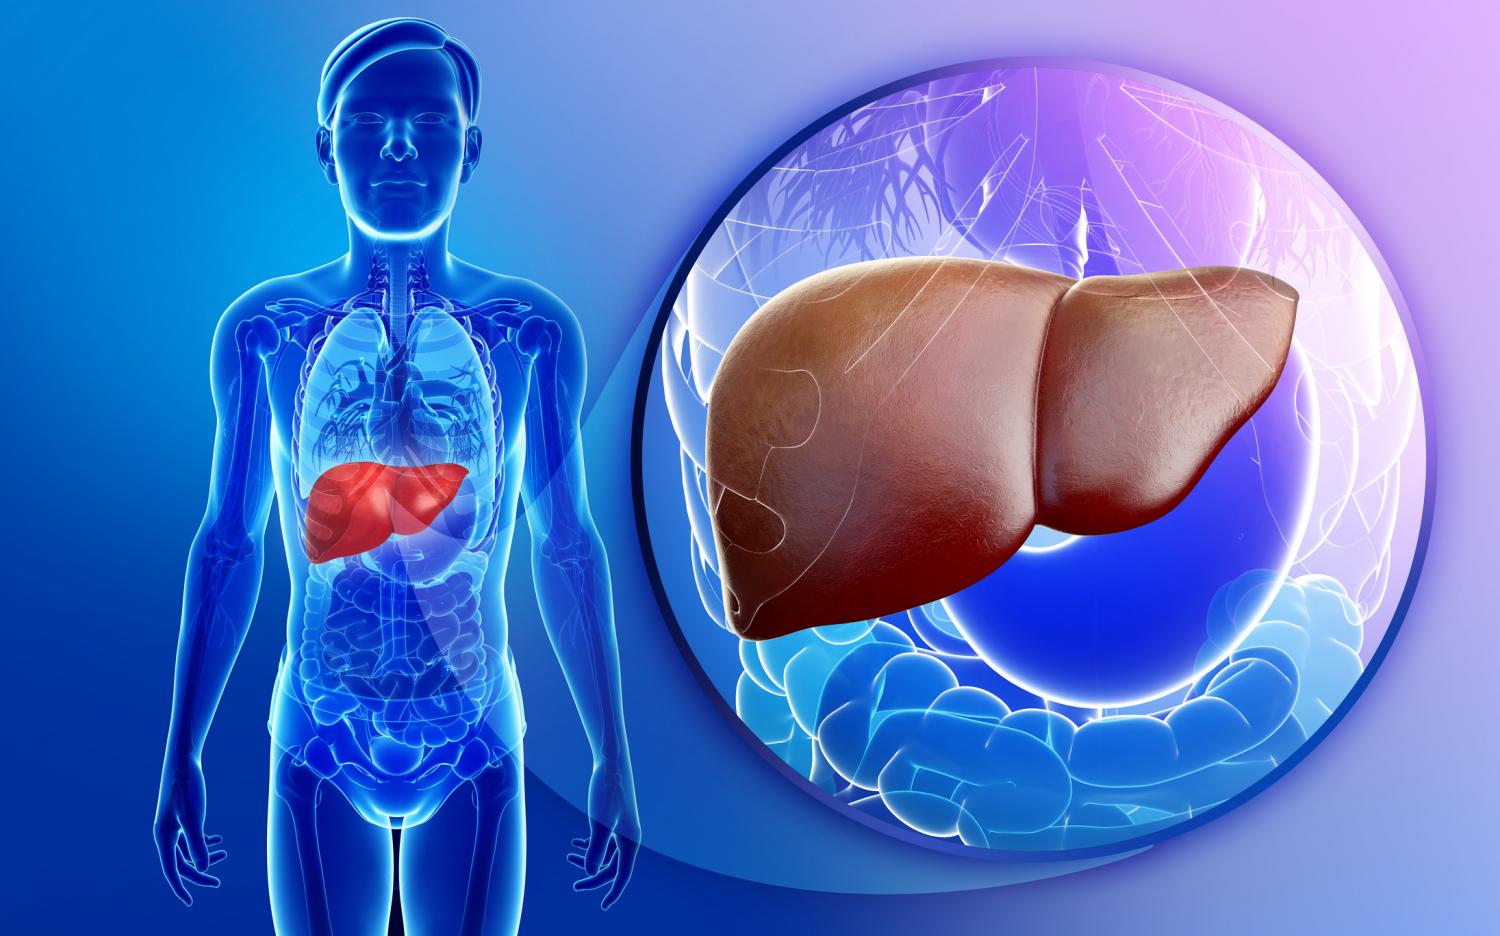

Изображения заболеваний печени: признаки и симптомы

Раздел: Пульс времени